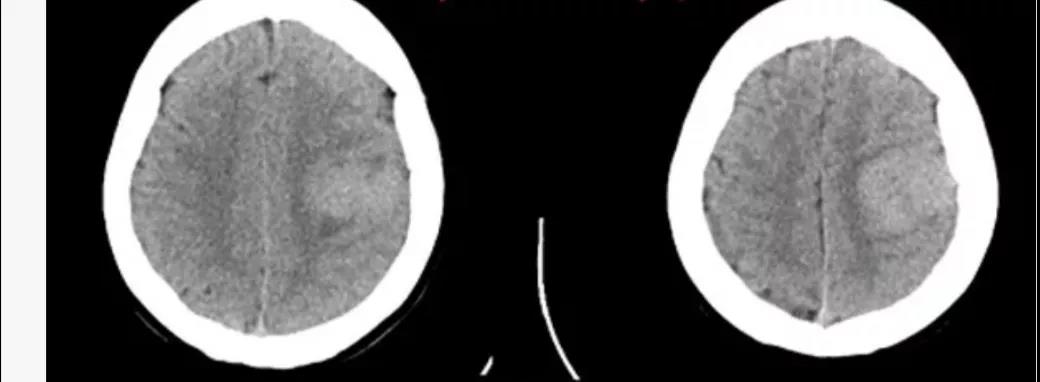

患者,58岁,渐进性头疼1年余,遂来我院就诊。入院后行头颅CT、MR示左侧顶叶占位性病变,经接诊医师李明详细说明病情后家属决定于我院进行手术治疗。